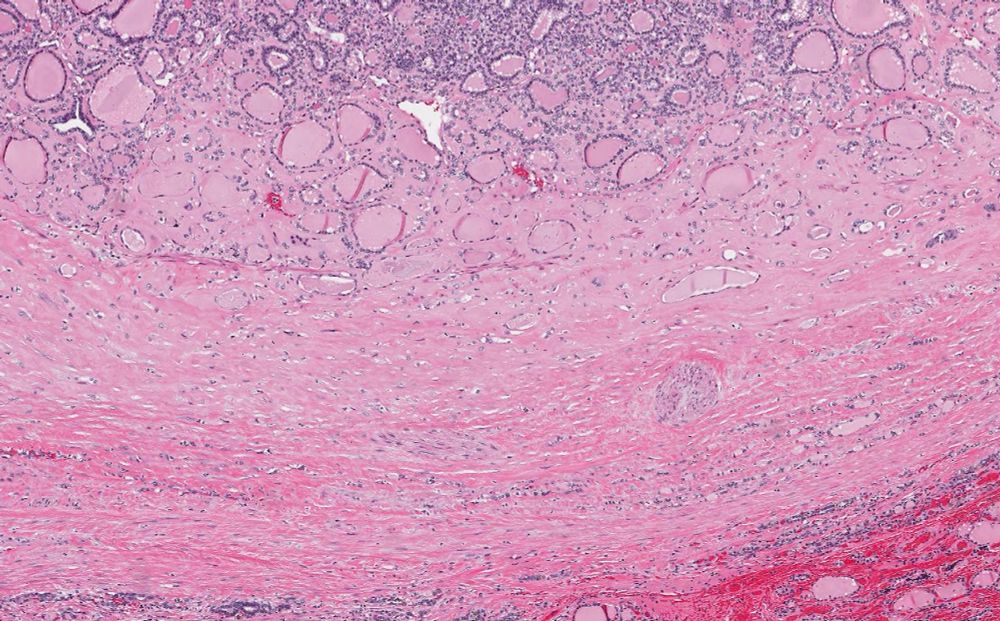

60’s male, parotid mass

Dx: Warthin tumor

πŸ“Έmacro: cystic-solid mass, note layering of cystic contents for gross-micro correlate [arrow]

πŸ“Έlow mag overview [arrow for gross-micro reference]

πŸ“Έpapillary projections w/lymphoid stroma

πŸ“Έbilayered oncocytic epithelium